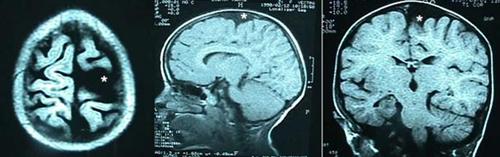

* Beyin yüzeyindeki araknoid kistler

Daha nadir görülen bu kistler bulundukları bölgede beyin dokusunda basıya ve kemikte incelmeye neden olurlar (Resim 9). Baş ağrısı epilepsi (sara) nöbetleri, bası yerine göre kol ve bacaklarda kuvvetsizlik görülebilir. Tedavide açık cerrahi ile kist duvarının alınması söz konusudur.

Resim 9: Değişik düzlemlerde elde edilmiş MRG kesitlerinde beyin yüzeyinde yerleşim gösteren araknoid kist (

*).